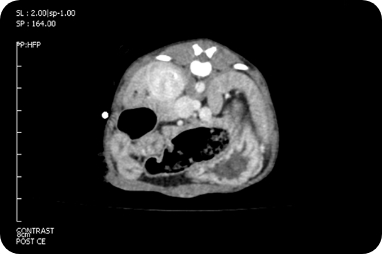

CT/3D-CT 검사

CT 검사는 방사선을 이용하여 신체 구조물의

단면을 영상화 하는 검사 장비로

눈으로

보기 힘든 부분을 정밀하게 볼 수 있으며,

혈관 조영 및 3D 재구성을 통해 수술과 같은

처치를 보다 안전하고 완벽하게 진행하는데

도움을 줄 수 있습니다.

복부

복강 내 종양 및 전이 평가,

복강 내 혈관 이상

복강종양